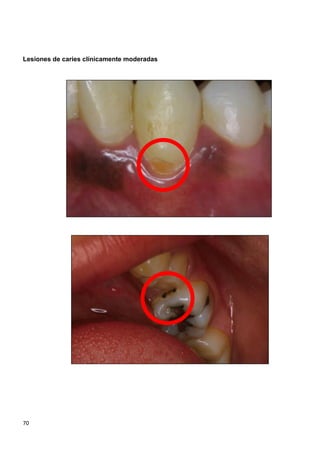

recomendado para niños ≤ 6 años. (SIGN 1---)

67,76

MNO: Sellantes a base

de resina/ionómero de

vidrio (SIGN 1+ / 1---)

65,79

MNO: Sellantes a base de

resina /infiltrantes

(SIGN 2--) 87

MNO: Higiene oral con crema dental fluorada (1000 ppm) cuando